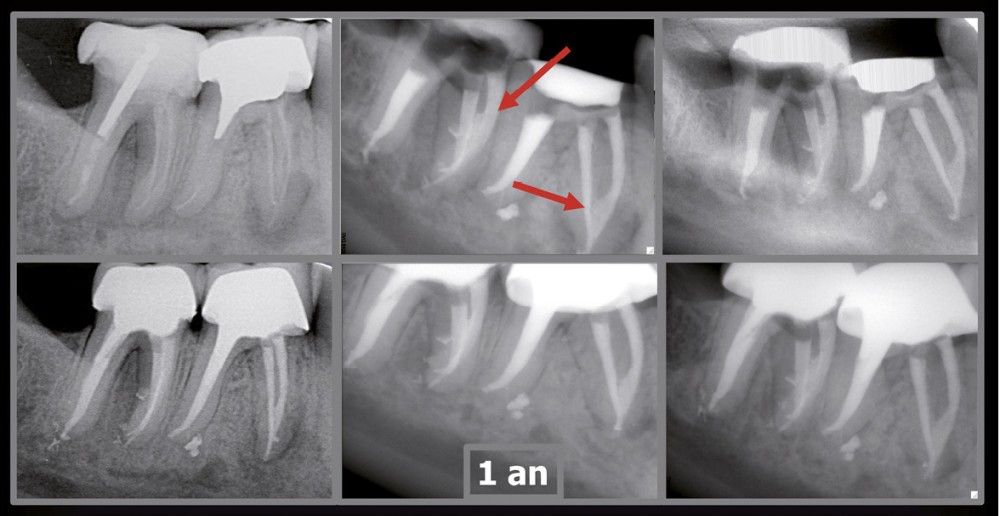

Endal, en 2011, montrait également, en utilisant le micro CT Scanner, l’insuffisance de nettoyage des isthmes inter-canalaires à nos techniques conventionnelles [19]. L’utilisation du laser Er:YAG devenait alors incontournable dans le nettoyage de ces isthmes et des zones non instrumentées (fig. 2 et 3).

Si l’étude de Peters [18] nous montre que l’instrumentation laisse 35 % du volume canalaire non instrumenté, Ricucci et Siqueira montrent que la préparation physico-chimique n’élimine que partiellement les tissus nécrotiques à l’entrée des canaux latéraux, des isthmes et des ramifications apicales, en laissant des tissus enflammés et infectés, en association avec des lésions apicales [29] (fig. 4 et 5).

Si les isthmes sont particulièrement mis en évidence au niveau des molaires mandibulaires, cela devient médicalement important au niveau des molaires maxillaires.

La diffusion bactérienne et de leurs toxines, au niveau des molaires maxillaires est à l’origine d’un grand nombre de sinusites maxillaires chroniques, d’origine dentaire. Celles-ci sont principalement causées par l’absence de traitement du deuxième canal MV, qui existe dans 90 % des cas, et il est à noter que ces deux canaux – MV1 et MV2 – sont également reliés par un isthme.

Le nettoyage des isthmes intercanalaires reste un réel problème, et semble responsable de nombreux échecs [43]. Par ailleurs, il est nécessaire d’utiliser des instruments qui évitent de propulser les débris, tant apicalement que latéralement, en obturant les entrées isthmiques avec des débris compactés.

L’utilisation d’instruments en nickel titane, tels que le XP Shaper (FKG), le Vortex blue (Dentsply) ou le Profile (Dentsply), optimise la remontée des débris et s’inscrit dans cette nouvelle philosophie. En conséquence, la combinaison XP Shaper, XP Finisher et l’irrigation avec l’Er:YAG semblent optimiser nos traitements [44,45].

Le passage du laser est répété plusieurs fois, en début, au milieu et en fin de préparation. Un protocole peut alors être proposé : 40 mJ ; 20 Hz (fig. 7). L’utilisation de biocéramiques Bioroot (Septodont) ou Total Fill R (FKG) permet de sceller le système ainsi nettoyé, en assurant une action biologique de longue durée [46] (fig. 8a à c).